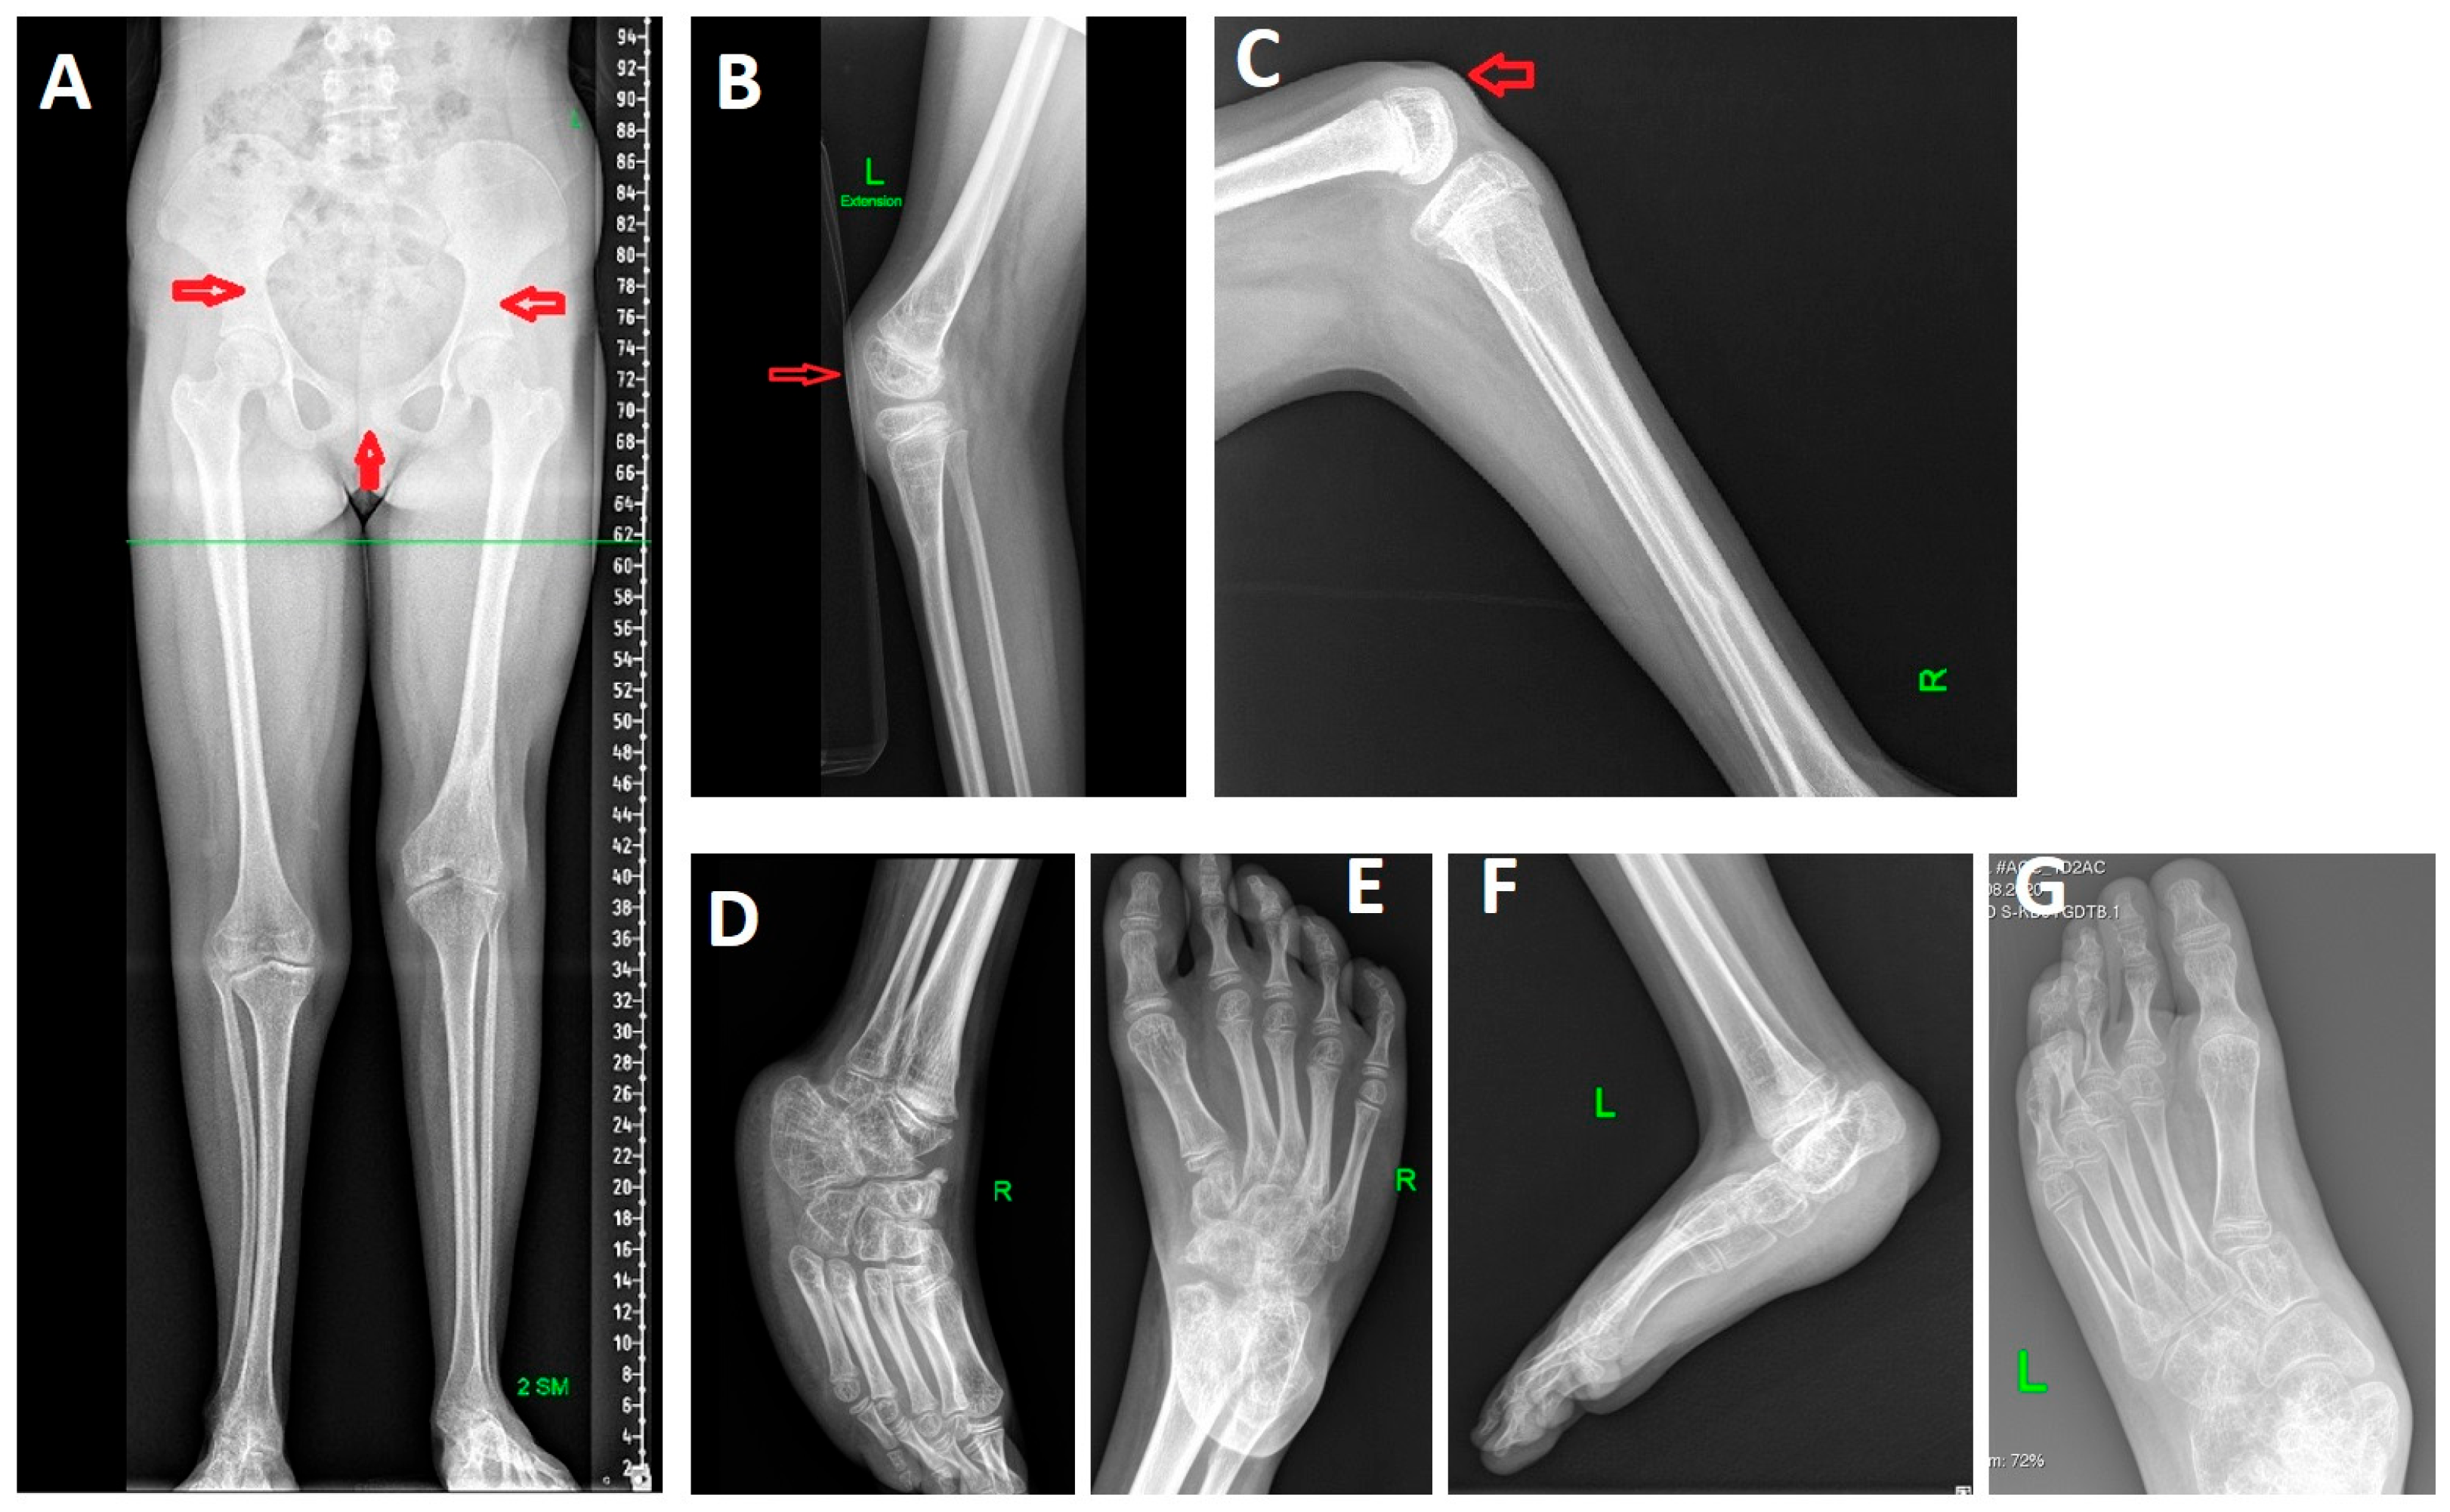

Radiographs of the lower limbs revealed 2-cm shortening of the left leg, atypical morphology of the iliac bones, a wide pubic symphysis, bilateral patellar aplasia, flexion contractures of the knees, foot deformities (Figure 2).

Figure 2. Radiographs of the proband’s lower limbs. (A) Panoramic anteroposterior radiograph of the lower limbs of a 17-year-old female patient. A shortening of the left lower limb by 2 cm is observed (4 cm in the right tibia and 6 cm in the left femur). The iliac bones exhibit an atypical shape, and the pubic symphysis is widened (indicated by red arrows). (B,C) Lateral radiographs of the knees of a 12-year-old female patient. Flexion contractures are present, measuring 70° on the right and 35° on the left. Bilateral patellar aplasia is evident (indicated by red arrows). (DG) Anteroposterior and lateral radiographs of the feet of an 11-year-old female patient. The right foot demonstrates an equinovarus deformity (D,E), while the left foot shows an equino–plano–valgus deformity (F,G).